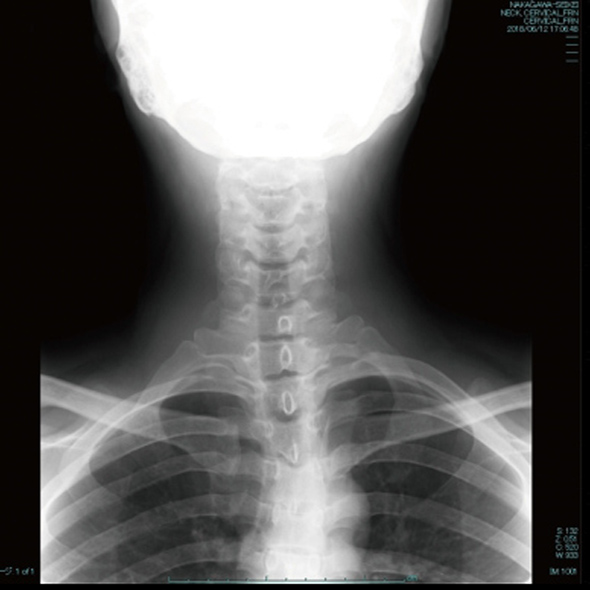

交通事故治療は画像診断が不可欠です。

レントゲンでは、骨折の症状に影響を与えるような経年性変化(加齢変化)を診断します。

事故の状況、痛みの部位、神経症状の有無などを丁寧に問診していきます。最新型MRIやレントゲン・エコーによる医師の画像診断の後に、理学療法士・鍼灸師・看護師によるチーム医療を行っていきます。